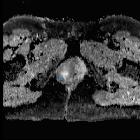

Vulvar

leiomyosarcoma in Bartholin"s gland. Heterogeneous, high-signal-intensity mass (asterisk) on high b-value DWI.

leiomyosarcoma in Bartholin"s gland. Heterogeneous, low-signal-intensity mass (asterisk), confirming the restricted diffusion on ADC map.